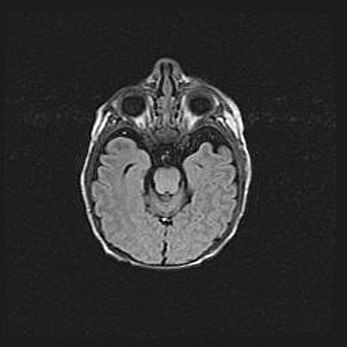

Мальформация Денди-Уокера. Киста задней черепной ямки.

Агенезия мозолистого тела.

Возраст: 2,5 месяца

Вес: 2420 г

Пол: женский

Окружность головы: 37 см

Срок гестации: 32 недели

Мальформация Денди—Уокера — редкий вид патологии ЦНС, представляющий собой врожденный порок развития каудального отдела ствола и червя мозжечка, ведущий к неполному раскрытию срединной (Мажанди) и латеральных (Лушка) апертур IV желудочка мозга. Для этогно синдрома характерна триада симптомов: гипотрофия червя мозжечка и/или полушарий мозжечка, кисты задней черепной ямки, гидроцефалия различной степени. В 70% случаев порок сочетается и с другими аномалиями головного мозга, в частности с агенезией мозолистого тела.